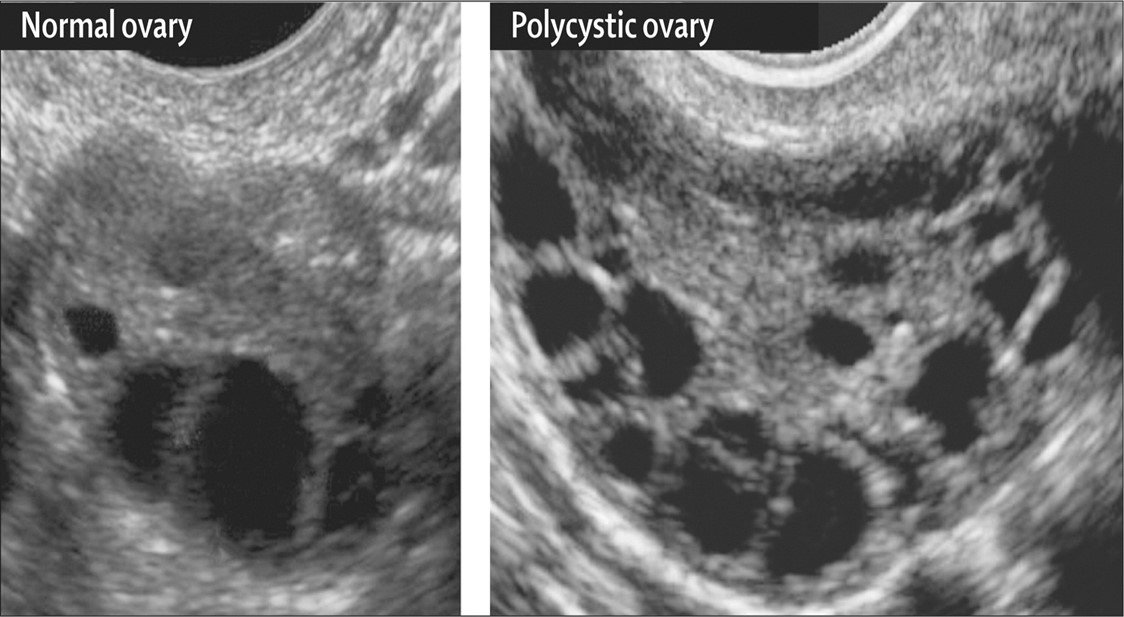

شکل تخمدان طبیعی و تخمدان پلی کیستیک

مقایسه تخمدان نرمال و تخمدان پلی کیستیک

3- شکل تخمدان در سونوگرافی (  به صورت تخمدان‌های پلی کیستیک با تعداد مشخصی فولیکول)

نمای تخمدان پلی کیستیک در سونوگرافی (تنبلی تخمدان)